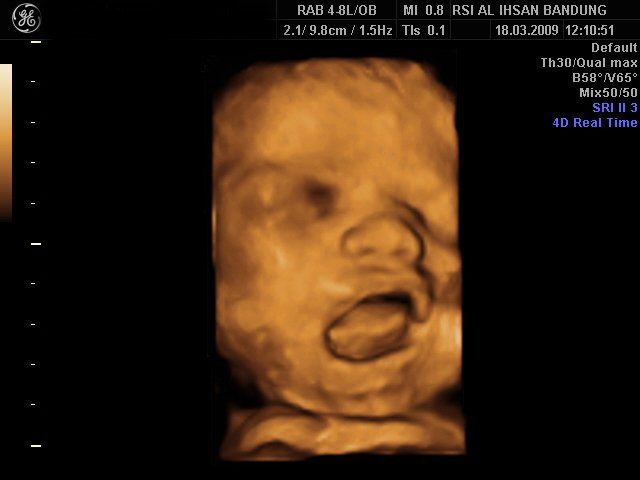

4D image of 29 weeks pregnancy, multiple anomalies: Clinch hand, omphalocoele, single atrium